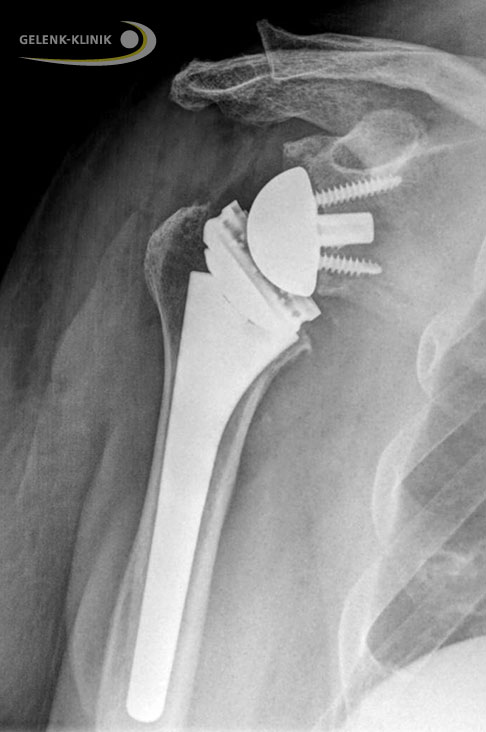

Dieses Prothesenmodell kehrt das biomechanische Prinzip des Schultergelenks um und vertauscht die anatomische Lage der beiden Gelenkpartner: Die dem Oberarmkopf ähnliche metallische Halbkugel wird an der Gelenkpfanne befestigt, die künstliche Pfanne wird an den Oberarmkopf angebracht.

Die inverse Schulterprothese verfügt über einen kugelförmigen Gelenkpartner an der Gelenkpfanne (Glenoid) des Schulterblatts und über eine künstliche Gelenkpfanne am Oberarmkopf (Humeruskopf). © Depuy-Synthes

Durch diese umgekehrte (inverse) Anordnung kommt es zu einer Verschiebung des Drehpunktes im Schultergelenk: Das Drehzentrums des Gelenkes verschiebt sich zur Körpermitte und nach unten. Der Abstand zwischen Oberarmkopf und Schulterdach wird dadurch vergrößert. Der Deltamuskel wird vorgespannt und kann die Funktion der Sehnen der Rotatorenmanschette teilweise übernehmen. Die Betroffenen sind so in der Lage, den Arm anzuheben.

Schematische Darstellung einer inversen Schulterprothese. Sie vertauscht Gelenkpfanne und Gelenkkopf miteinander. Dadurch verschiebt sich der Drehpunkt des Gelenks zur Körpermitte und nach unten (caudal). Der Abstand zwischen Oberarmkopf und Schulterdach vergrößert sich. Der Deltamuskel ermöglicht den Betroffenen, den Arm anzuheben. © Gelenk-Klinik

Röntgenbild einer inversen Schulterprothese. © Gelenk-Klinik